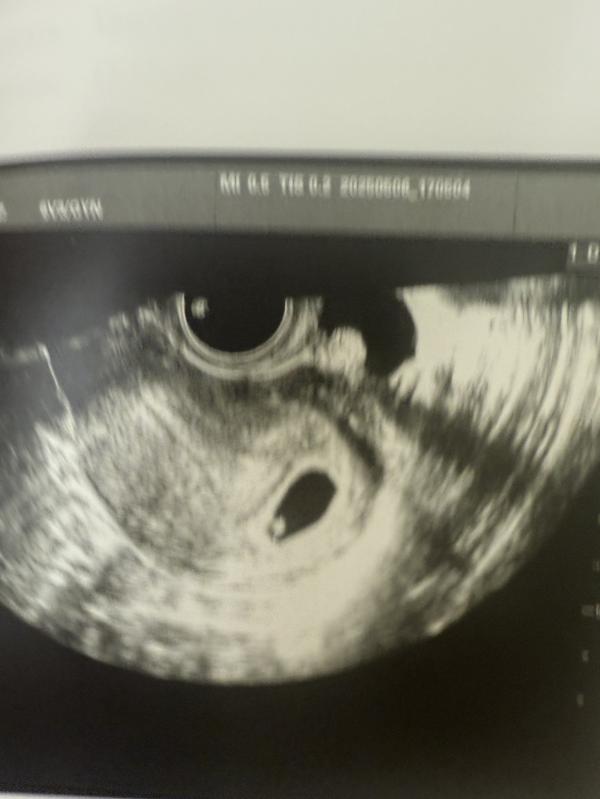

После потери становишься очень уязвимым.. Утром грудь стала мягкой, до этого хорошо ощущалась наполненность,болезненность. Я не выдержала и сходила на узи. Срок по месячным 6,1, по узи поставили 5-6, сб не нашли, предположили лишь по сокращению эмбриона.. Жду еще неделю и надеюсь услышать сердечко своей долгожданной крошки.